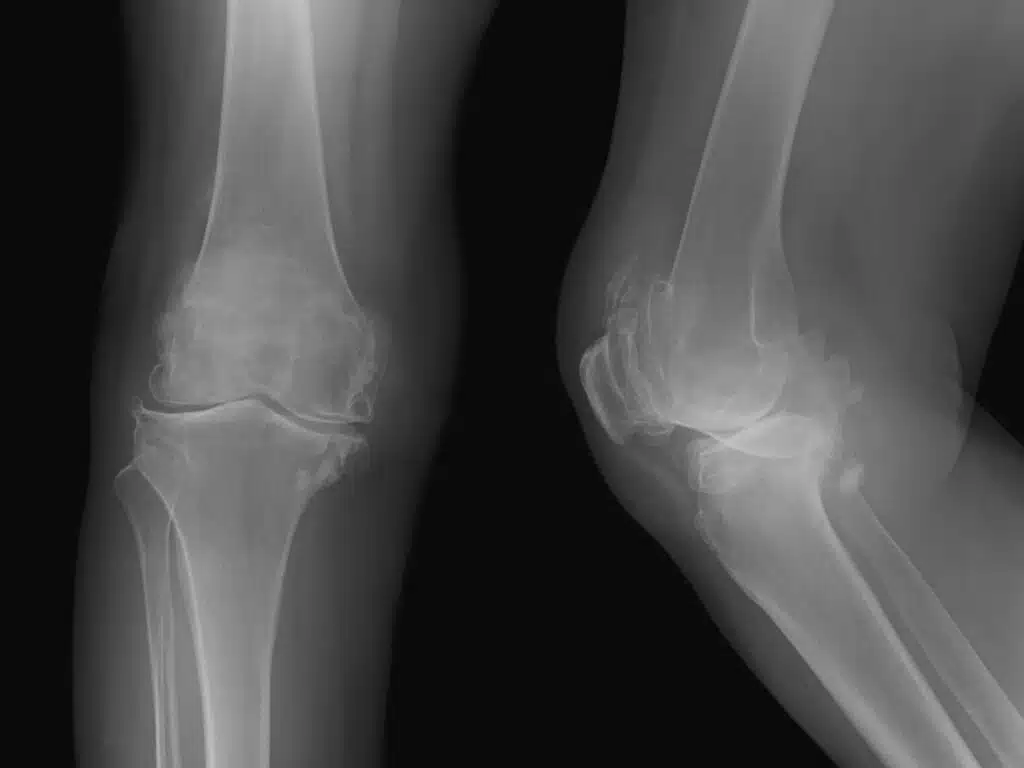

Kniearthrose-OP in vielen Fällen vermeidbar?

Wissenschaftler in den USA untersuchten OP-Alternativen für Arthrosepatienten – mit bahnbrechenden Ergebnissen.

Studie lesenKniearthrose: Werden zu viele Knieprothesen eingesetzt?

Bei Kniearthrose kann der Einsatz eines künstlichen Gelenks oft verhindert oder hinausgezögert werden – ein aktueller Report klärt auf.